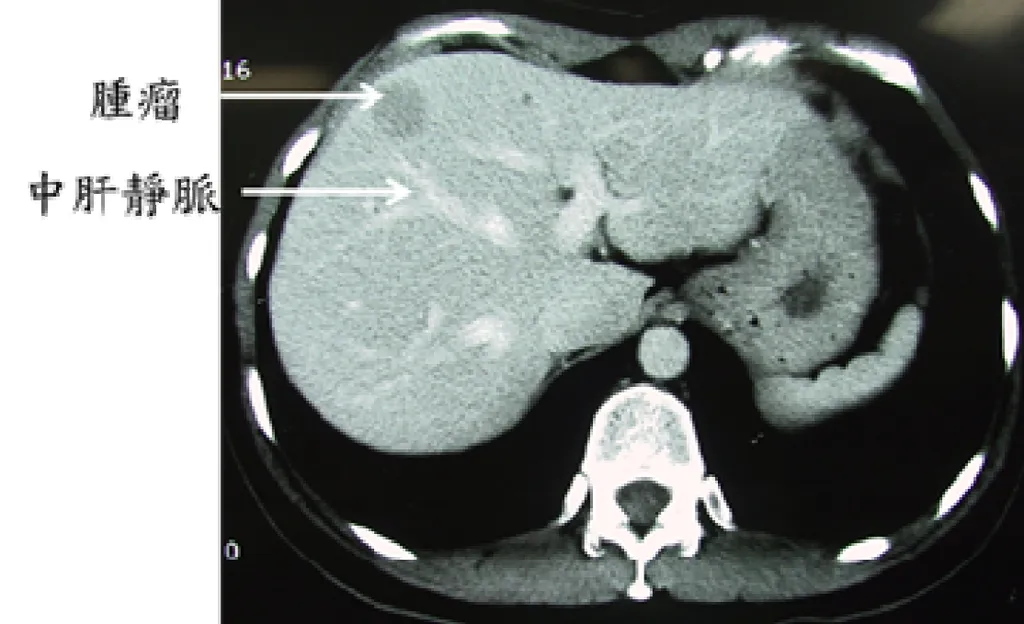

詳解

破題關鍵

這題的解題核心在於精準辨識肝臟電腦斷層影像上的Couinaud分葉,關鍵是利用中肝靜脈(middle hepatic vein)作為分界線,並判斷腫瘤相對於這條線的位置。

選項拆解

登入查看完整詳解與互動作答